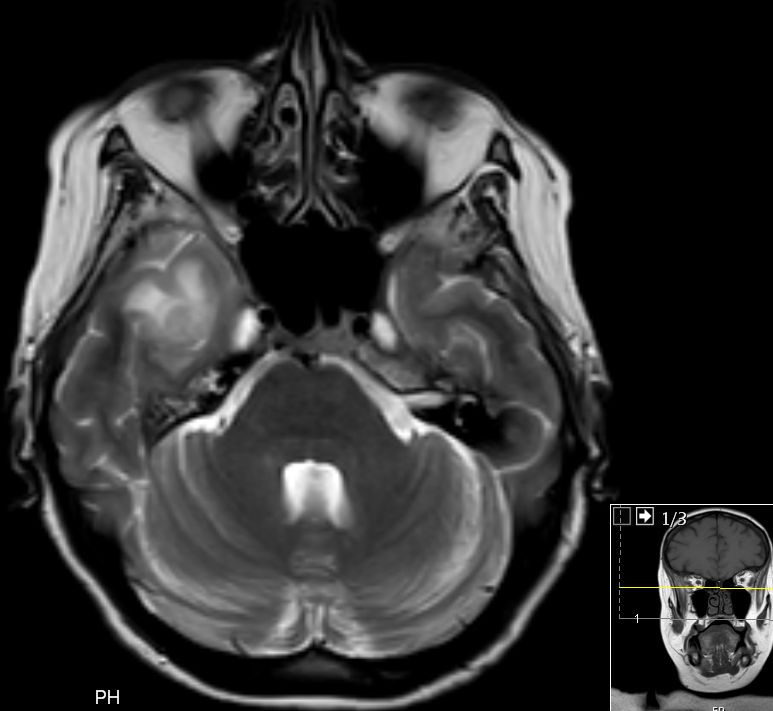

| Schädelbasis | 62-jährige Frau, bei der vor 2 Monaten ein Plattenepithelkarzinom der Zervix FIGO IIIB mit Radiochemotherapie behandelt wurde. Die Uterusgröße hatte von 13 auf 6 cm abgenommen. Jetzt Aufnahme mit der Diagnose Apoplex. | |||

An der Basalfläche des rechten Temporallappens KM - aufnehmende RF.![]()  |

Unklare Doppelkontur der Meningen des Halsmarks.![]()  |

Ödem des rechten Temporallappens.![]()  | |||